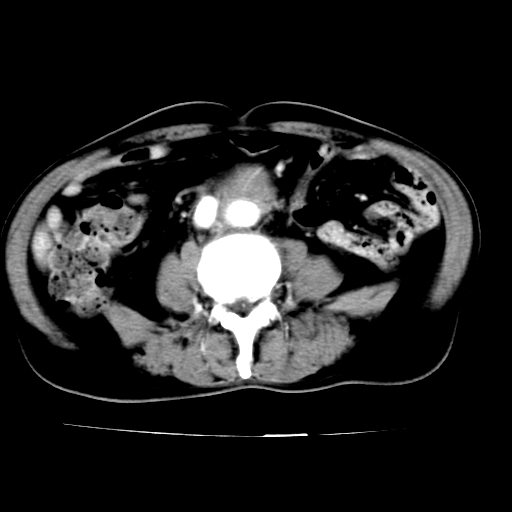

标题: V0243:右髂总动脉瘤附壁血栓形成?破裂?动静脉瘘? [打印本页]

标题: V0243:右髂总动脉瘤附壁血栓形成?破裂?动静脉瘘?

男,75岁,腹痛月余,彩超发现脐周腹主动脉异常回声。临床诊断:腹主动脉瘤。

ct诊断:右骼总动脉囊性动脉瘤并瘤内附壁血栓形成,与下腔静脉之间形成动静脉瘘。

请问各位老师:能排除动脉瘤破裂的可能吗?

各位老师注意到下腔静脉的充盈缺损了吗?注意到动静脉漏了吗?

当时是扫描的标准动脉期,可是下腔静脉与腹主动脉同步强化且幅度一致。所以我想动静脉瘘是存在的。